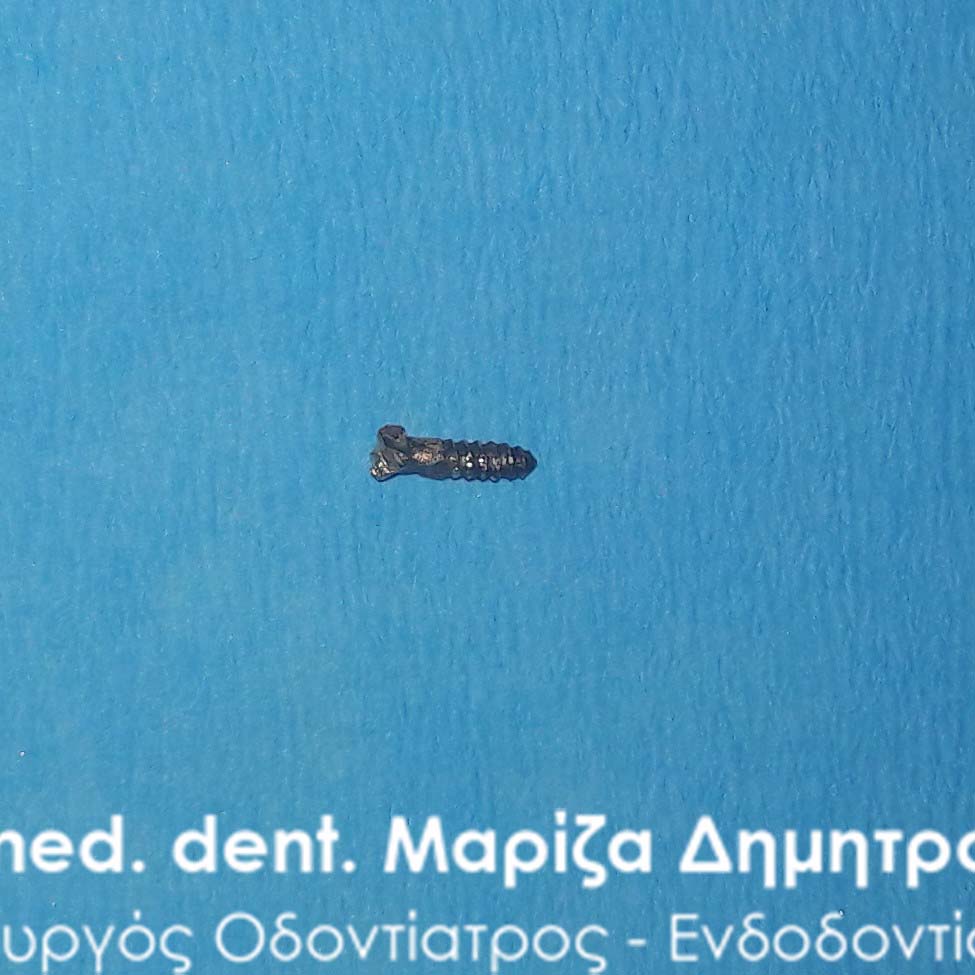

The metallic stift after removing it from the tooth